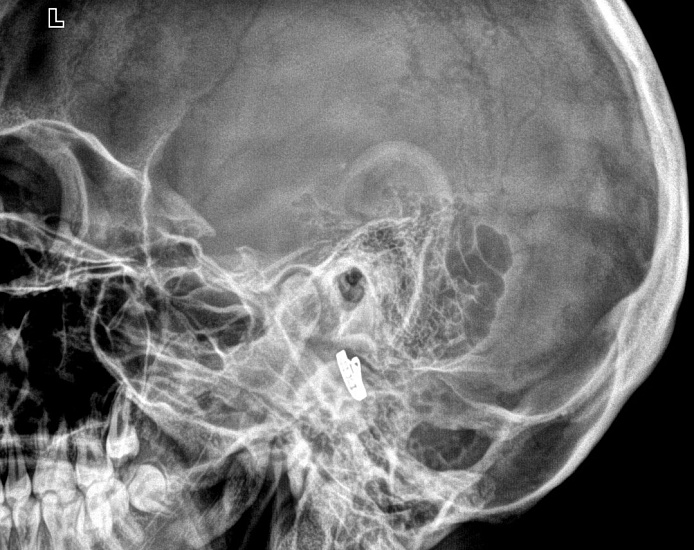

1. Рентгенография височных костей в поперечной проекции (укладка по Стенверсу)

Прицельное исследование пирамиды височной кости, ее верхушки и внутреннего слухового проход.

2. Рентгенография височных костей в косой проекции (укладка по Шюллеру)

Прицельное исследование структуры сосцевидного отростка, височно-нижнечелюстного сустава, выполняется в одной проекции.